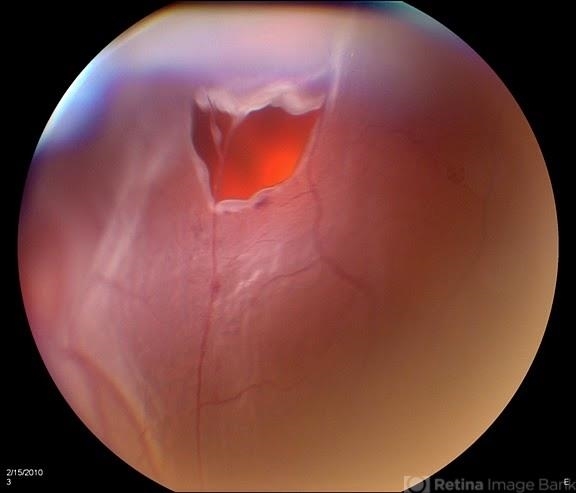

- retinal tear

- Patient came in with curtain appearing in the superior part of vision. Retinal tear superior visible with detachment. Surgery is scheduled.